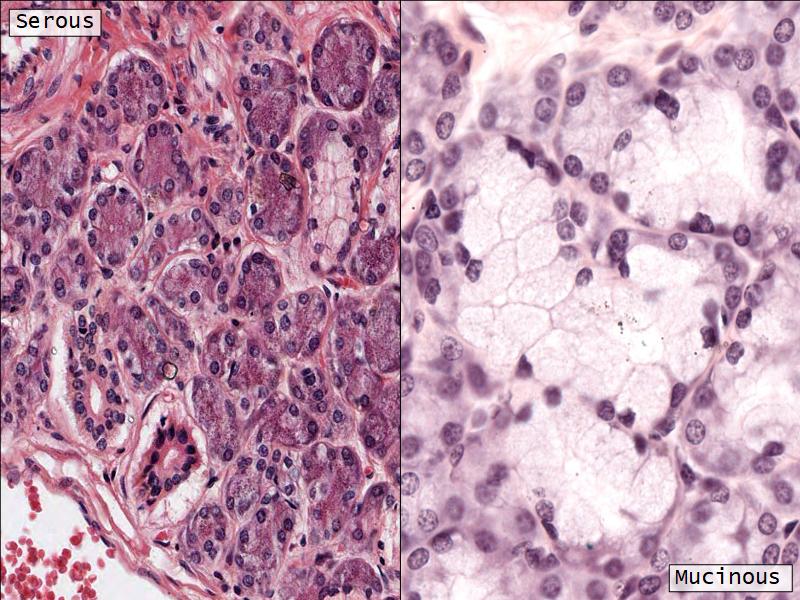

Cancer Association of South Africa (CANSA):Q03 - 1

List 2 types of exocrine secretions:

- Serous

- Mucinous

Mucinous and serous secretory units from the Virtual Microscopy Database at http://virtualmicroscopydatabase.org/

Title: Salivary Gland, Sublingual, Human

Title: Submandibular Gland

Owner: H Goldman

Drexel University - Collection Gastrointestinal System

Used under the BY-SA-NC Creative Commons License